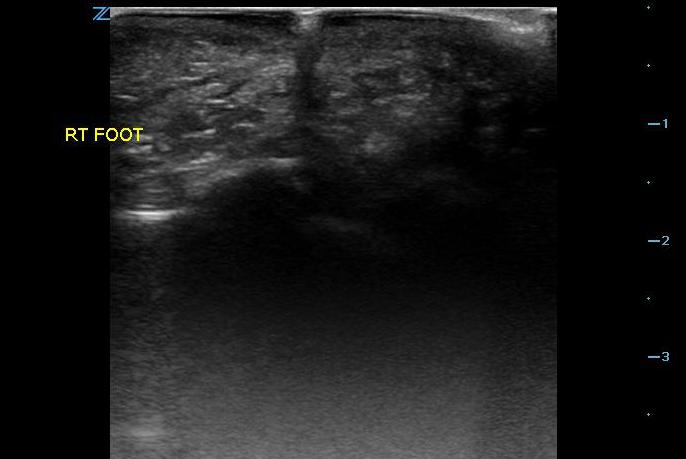

- Figure 2. Glass in foot with shadowing

- Material such as wood, glass, and plastic tends to produce shadowing (Videos 2-4 and Figure 2) which will be visualized in the tissue deep to the foreign body.

- Foreign bodies will usually appear hyperechoic to the surrounding soft tissue.

- The area is scanned throughout its entirety in search for a hyperechoic object in both the sagittal and transverse planes as it can sometimes be much easier to visualize an object in one plane but not the other. Be aware of possible surrounding tissue inflammation or abscess.

- Once a foreign body is localized, the depth from the skin can be measured as well as the size of the object.